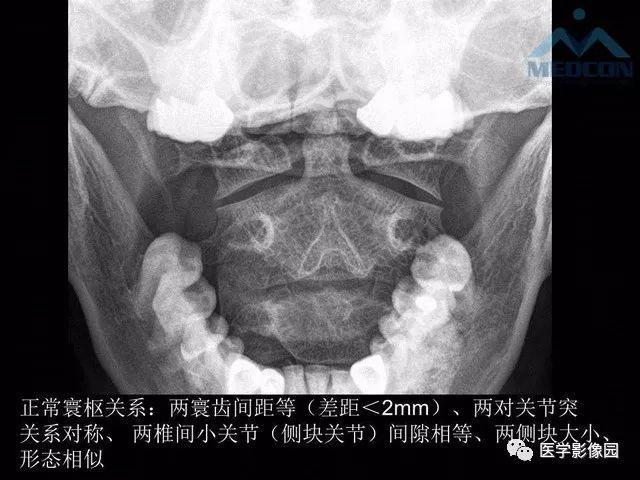

寰枢关节脱位的影像诊断